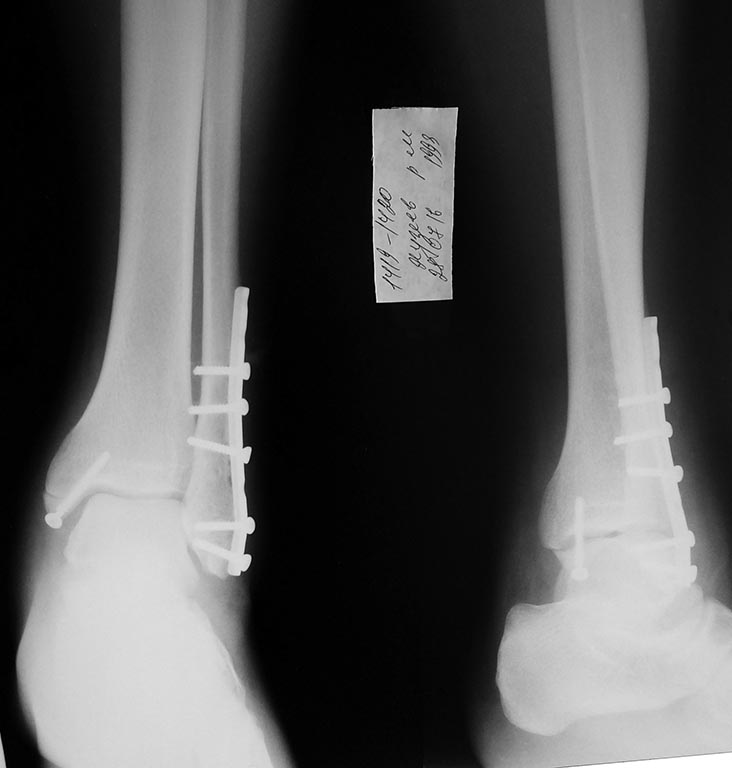

[Ortho] Разрыв межберцового синдесмоза

Через послеоперационную рану удалил проксимальный винт, откусил

кусачками  пару миллиметров